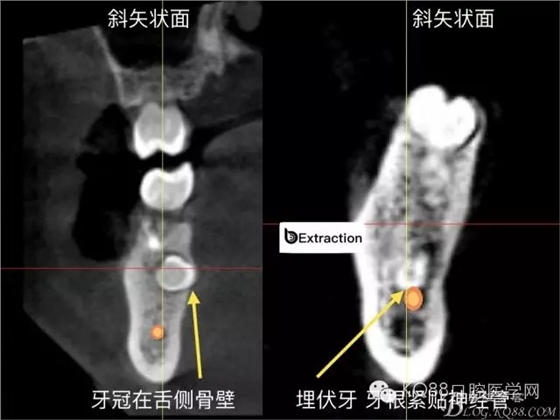

精準(zhǔn)拔除術(shù): 下頜高風(fēng)險(xiǎn)埋伏牙